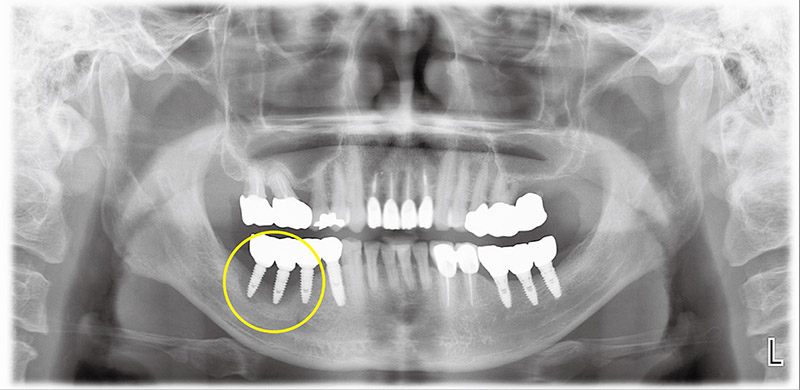

결국 맨 뒤 임플란트 세 개를 제거하고 3개월이 지나 잇몸이 다 낫고 나서 충분한 높이와 두께로 다량의 골이식을 시행하였다. 또한 이식된 뼈가 주변잇몸의 압력으로 인하여 흡수되는 것을 방지하기 위해 금속막을 이용하여 공간을 형성, 6개월 후 금속막을 제거한 후 새 임플란트를 식립했다. 다음 사진(그림2)은 임플란트 식립이 완성된 상태에서 촬영한 파노라마다.